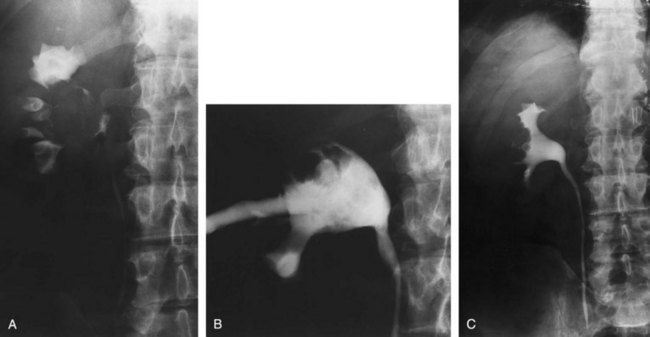

Although intravenous pyelography has been the traditional means for diagnosis of upper tract lesions, computed tomographic (CT) urography is increasingly performed today. CT is easier to perform and less labor intensive than intravenous pyelography. It also has a higher degree of accuracy in determining the presence of renal parenchymal lesions. On the other hand, small urinary filling defects (<5 mm) may be missed between the “cuts” of the traditional CT scan. More recently, CT urography has been performed to obtain a three-dimensional image of the upper tracts. This technique appears to be equal to intravenous pyelography in imaging the ureters and renal pelvis (McTavish et al, 2002). With CT urography, the sensitivity for detecting upper tract malignant disease has been reported to approach 100%, with a specificity of 60% and a negative predictive value of 100% (Caoili et al, 2002). CT urography does, however, expose the patient to higher doses of radiation.

Radiolucent filling defects, obstruction or incomplete filling of a part of the upper tract, and nonvisualization of the collecting system are the typical findings suggestive of an upper urinary tract tumor. Filling defects, which account for 50% to 75% of cases, typically require the intravenous administration of contrast material to be identified (Murphy et al, 1981; Fein and McClennan, 1986). The differential diagnosis of these defects includes blood clot, stones, overlying bowel gas, external compression, sloughed papilla, and fungus ball. Stones can be ruled out most easily by confirmation of calcification by renal ultrasonography or CT. TCCs have an average density of 46 Hounsfield units (HU) and a range of 10 to 70 HU (Lantz and Hattery, 1984). This is in contrast to an average of 100 HU seen in radiolucent uric acid stones (range, 80 to 250 HU). Thus CT can be useful in distinguishing between these two common causes of radiolucent filling defect on excretory urography or retrograde ureterography. The impact of hydronephrosis and nonvisualization for renal pelvis tumors versus ureteral tumors as indicators of a higher stage is uncertain. Nonvisualization is reported in 20% of renal pelvis tumors, only 33% of which are invasive (McCarron et al, 1983). Nonvisualization is reported in 37% to 45% of ureteral tumors and carried a 60% risk of invasion in one series (McCarron et al, 1983). In other reports there is no correlation of nonvisualization and stage (Batata and Grabstald, 1976; Anderstrom et al, 1989). Hydronephrosis with or without an associated filling defect is linked with invasion in 80% of ureteral tumors (McCarron et al, 1983; Cho et al, 2007).

Radiolucent, noncalcified lesions may require additional evaluation by retrograde urography or ureteroscopy, with or without biopsy and cytology. Overall, retrograde urography has an accuracy of 75% in diagnosis of an upper tract malignant neoplasm (Murphy et al, 1981). An incompletely filled or obstructed renal infundibulum or calyx, occurring in 10% to 30% of cases, again typically requires retrograde urography or ureteroscopy to confirm the diagnosis. Obstruction of the urinary tract is a poor prognostic sign for tumor invasion (Babaian and Johnson, 1980).